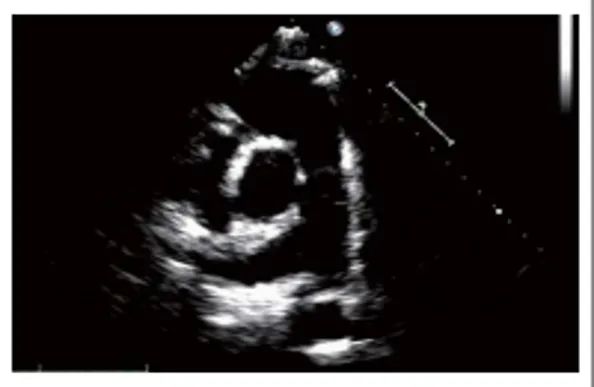

心尖四腔心切面

探头位置:探头置于心尖搏动点处;探头指向右胸锁关节。

观察内容

● 瓣膜活动:二尖瓣及三尖瓣形态结构与活动。

● 腔室大小:左房,左室,右房,右室。

● 室壁运动:左室壁的侧壁和后室间隔。

● 室壁厚度:左室壁的侧壁和后室间隔。

● 结构的连续:房间隔和室间隔。

● Simpson心功能的测定。